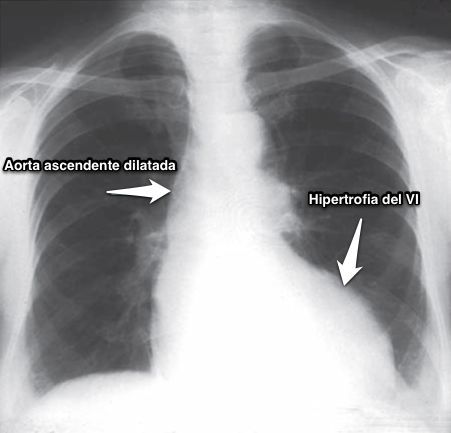

- Corazón de tamaño normal.

- Aorta ascendente dilatada☤.

- Calcificación☤ valvular aórtica.

- Hipertrofia del VI.